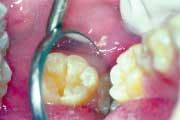

Because the failure rate among sealants is so high, we meticulously examine each sealant our patients have. The examination includes placing a caries-detection dye on the sealants using high resolution video-imaging. If a sealant is leaking, good magnification will show the tint of the dye under the sealant. A failed sealant is then easily removed, utilizing the parallel water stream technique. The operative field is flooded with water, while air abrasion is simultaneously used to selectively remove the sealant.

Micro-air abrasion increases profits to the dentist by providing more aesthetic restorations with greater patient acceptance due to the reduced need for local anesthetic. Highly destructive traditional preparations are no longer necessary when adhesive technology is utilized.

Patients are showing a great demand for conservative dentistry. Micro air abrasion has opened up a whole new method of treatment for them that preserves far more tooth structure than was ever previously possible. The resulting surfaces also are better prepared to receive and retain bonded restorations, compared to previous traditional methods of preparation.